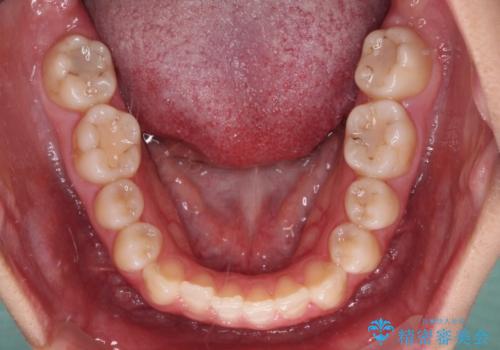

- 前歯の開咬と、上顎前歯の八重歯やデコボコを気にして来院された患者様です。

上顎歯列が狭窄していたため、急速拡大装置により上顎骨を側方に拡大し、その後ワイヤー装置にて矯正治療を行うこととしました。

上顎骨を拡大することで、八重歯やデコボコを歯列に収めることができ、下顎の歯が外に位置していた奥歯の咬み合わせも改善することができました。

スペースも短期間に獲得できるため、1年程度で治療を終えることができました。